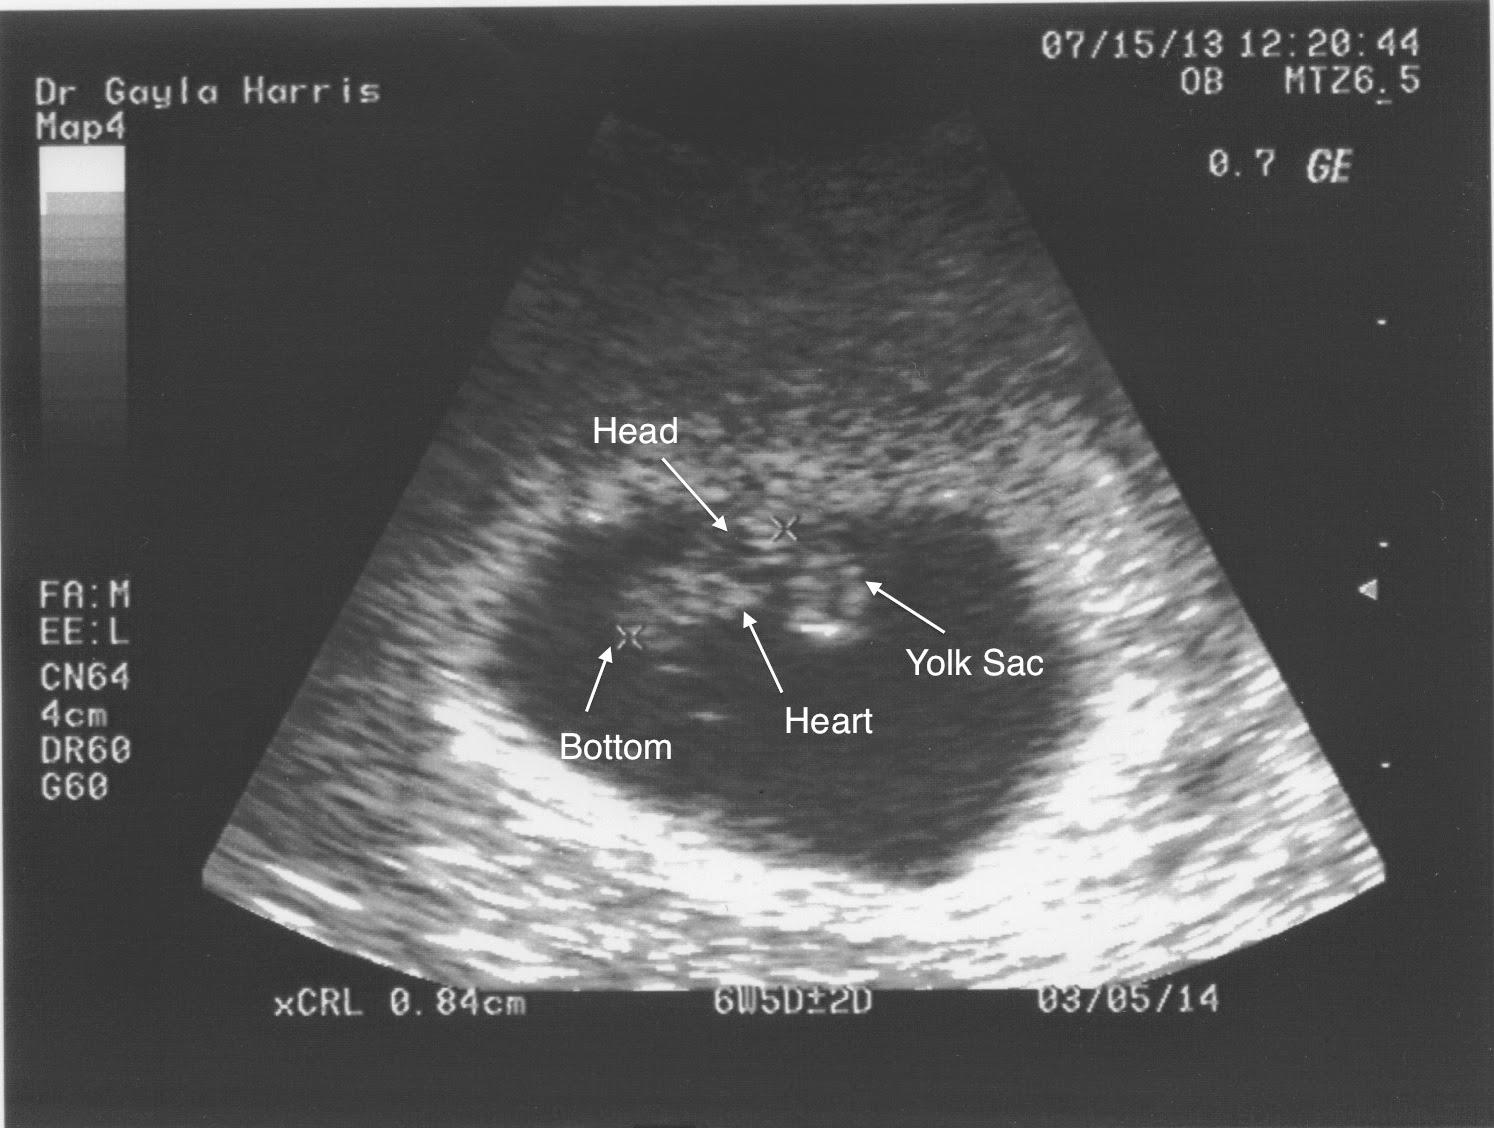

I went in for an ultrasound, to see if the embryo was in the right place, and it was. This little "bean" had made it through the tube, and had attached itself perfectly. I was measuring at 6 weeks, which was odd, considering that the date of my last period meant that I should be 4 weeks along. Regardless, I was PREGNANT!!! My elation was short-lived, though, as the doctor became concerned that she saw no movement or heartbeat. It turned out that my last "period" was actually the scary kind of bleeding that indicates a problem with the pregnancy. I was actually 8 weeks along, and had lost the pregnancy at 6 weeks. People who hear this story are always very sympathetic and sad over the loss of this pregnancy. I remind them, though, that, while it was a little heartbreaking in the moment, it was actually really good news. Contrary to all the medical opinions I had received, it was possible for me to get pregnant. And now that we knew that, my RE could help us with our baby-making schedule, and could provide the appropriate hormonal support.

So, after having to take Misoprostol to deal with the missed miscarriage, we started trying to conceive, with the help of my fabulous doctor. I'll skip past all the remaining gory details and just tell you that, on June 19, 2013, this happened:

and then, over time, this happened: